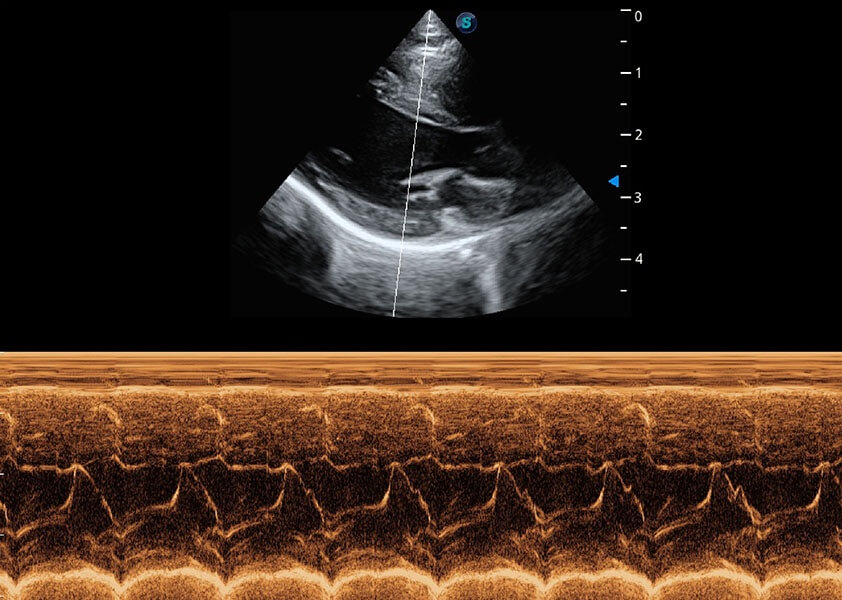

ProPet 60 作为一款高端台式动物超声设备,为动物医生的日常诊断提供了一系列贴合动物临床需求、解决临床实际问题的高级成像功能。凭借全系列高清探头,满足医生对腹部、心脏、生殖、浅表、肌骨等成像的所有需求,切实帮助您提升检查效率,提高诊断信心。